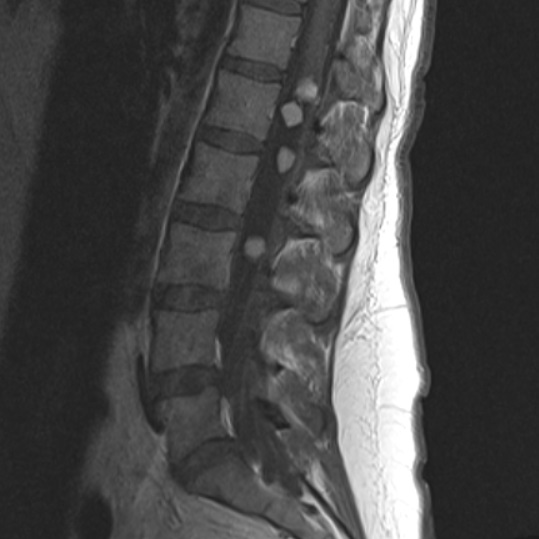

診斷

1、MRI檢查:診斷脊髓腫瘤較重要的檢查,可明確病變部位、范圍及脊髓形態(tài)變化,且增強掃描有助于定性診斷。

2、X-線和脊柱CT:提供脊髓腫瘤的間接征象。

3、脊髓血管造影:了解脊髓血管性腫瘤(如血管母細胞瘤)的供血及回流情況,有助于手術治療。